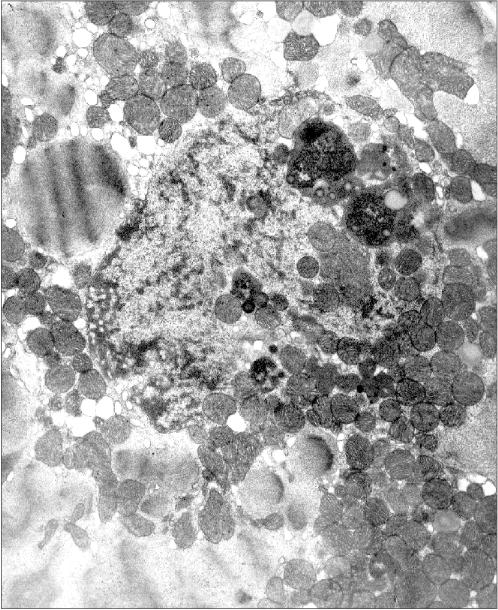

Figure 3 presents a section of a cardiomyocyte from a rat that was given ethanol and the catalase inhibitor aminotriazole for 12 weeks. Two mitochondria are clearly seen inside the nucleus. It should be emphasized that this model is well reproducible: five animals were treated as described above, and in four of them mitochondria were found inside the nuclei. This allows one to analyze the mechanism of such a phenomenon because in the previous studies the uniqueness of the object of study was a significant obstacle: the phenomenon was observed only in single cases. It should also be added that even in cases when intranuclear mitochondria were detected, the overwhelming majority of sections across nuclei did not reveal mitochondria. Thus, it is easy to understand why the mechanism and probable functional implications of this phenomenon remained virtually unexplored for more than 40 years.

Figure 3

Fig. 3. Intranuclear location of mitochondria in cardiomyocytes of an “alcoholic” rat; ×95,200.